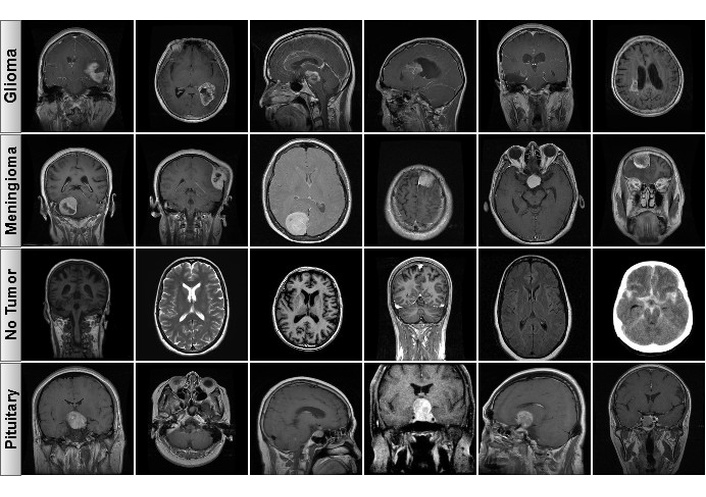

The data infrastructure for this research is referred to as the “Brain Tumor MRI Dataset”, which consists of a dataset created by Ahmed Sorour that is publicly available on Kaggle [38]. This dataset is a source of reference material for brain tumor classification and includes three common tumor classes: Glioma, Meningioma, and Pituitary. There is also a control group consisting of healthy brain MRIs with no tumor. There is a total of 5,249 T1-weighted, contrast-enhanced MRI slices that are noted as to their pathological state or normal. Figure 1 includes samples of the classes to illustrate the types of data included in the dataset.